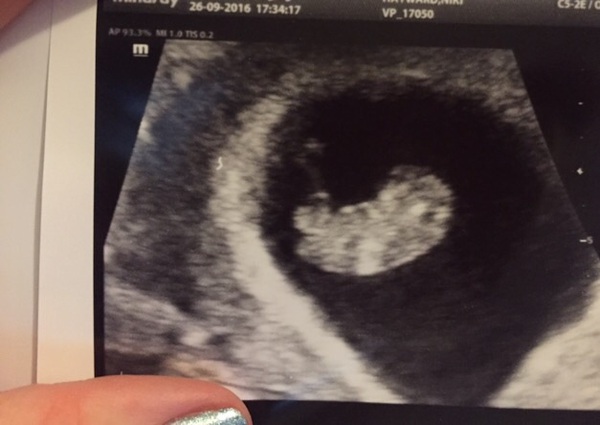

I had a private scan yesterday. Was amazing seeing my wriggly little blob Smile I'm 9w1d today and have had awful nausea. Gone completely off food. Boobs very sore and massive. And by the end of the day I've got a bloated little pot belly and it is very obvious!

Oh Niks that is a great scan image, it's pretty clear! Makes it more tempting to get one but I still think I'm going to hold off for now anyway.

Oh Niks that's amazing, I've just had one yesterday at 8+1 and I'm amazed at the difference a week makes.

That's a great picture Niks, have mine tomorrow, can't wait.

I had dating scans with my girls pregnancies for different reasons and couldn't wait for the 12week scan with this one so we paid £70 for a private scan. I've got about 20 photos and a usb stick with moving images :) was amazing and totally worth the money especially for the reassurance that everything is fine.

Icoco what does your scan look like at 8 weeks? It is incredible how different they look week by week isn't it.

Niks it wasn't as defined, mine was more round, whereas yours has a baby shape. I don't have a picture as it was an emergency NHS scan but I was shocked how clear the heartbeat was. We were originally booked in for a private scan on Thursday as I thought it was closer to 9wks and would be more defined. It's such a great feeling. Smile